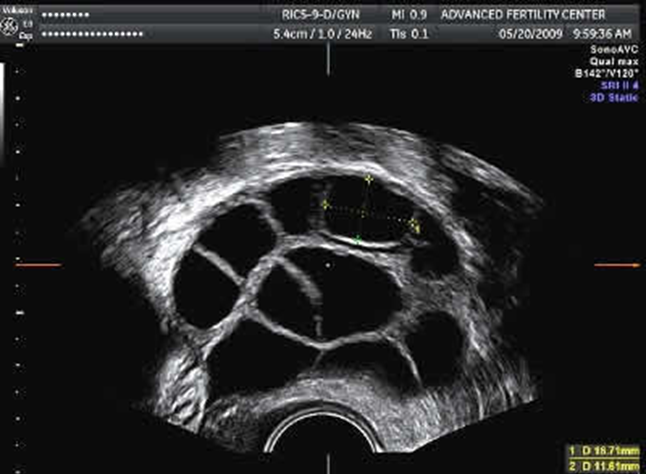

PGD involves the use of assisted reproductive technology (ART). Eggs are obtained and fertilized through in vitro fertilization (IVF). Once fertilized, the embryos develop for 5-6 days and then a number of cells are removed from each embryo. The genetic material (DNA or chromosomes) within these cells of the embryo is then tested for the genetic or chromosomal abnormality. An unaffected embryo is then transferred to the woman’s uterus to implant. If successful, the procedure will result in pregnancy and the child should not be affected by the condition for which it was tested.

• Trophectoderm biopsy of blastocysts